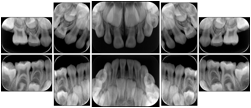

In most standard cases, images are oriented in structured layouts. These structured displays are useful to be shared between providers for reference purposes.

Table OO.1.1-1 shows structured display standard templates, where Viewset ID is based on the Japanese Society for Oral and Maxillofacial Radiology (JSOMR) classification provided by JIRA (Japan Medical Imaging and Radiological Systems Industries Association, www.jira-net.or.jp). Expected or typical teeth to be imaged location, region and designation codes are based on ISO 3950-2010, Dentistry - Designation system for teeth and areas of the oral cavity. For all the hanging protocols listed in OO.1.1-1, the value to use for Hanging Protocol Creator (0072,0008) is "JSOMR" and the value to use for Hanging Protocol Name (0072,0002) does not include "JSOMR" (e.g., "DL-S001A", not "JSOMR DL-S001A").